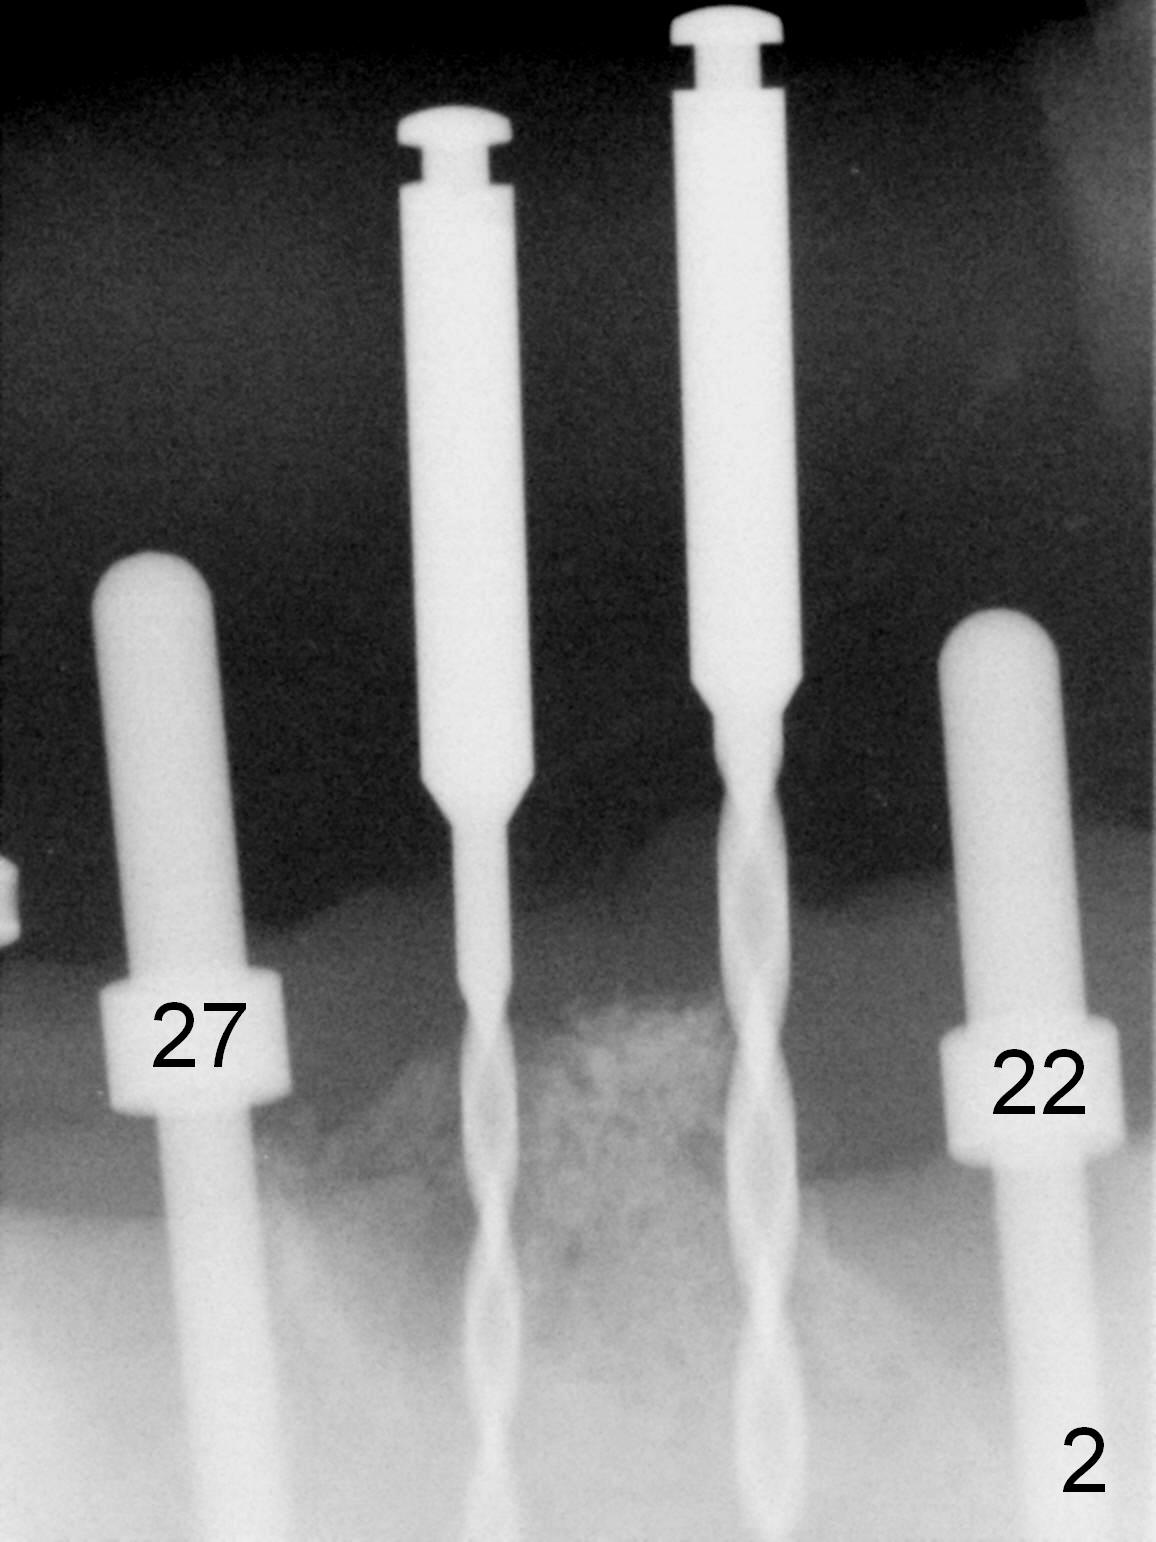

As expected, the bone density in the mandibular anterior region is found to be high during initial osteotomy (Fig.1-3). Five implants are placed at the sites between #22 and 28 (Fig.4,5): 3x14(2) mm 1-piece (bone-level) implants in the incisor region; 4.5x17 mm 2-piece (tissue-level) ones in the canine/premolar area. All of the implants are placed as lingual as possible. Bone graft is placed (*). Red dashed line: the superior border of the Inferior Alveolar Canal. Immediate splinted provisional bridge is fabricated. One week postop, periodontal dressing remains attached to the provisional and the gingiva.